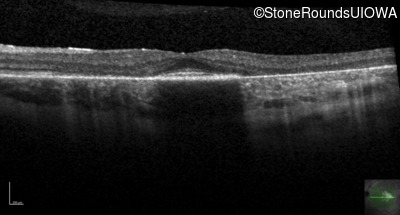

This 30 year old man first noticed poor vision in dim light when he was five years old. His visual acuity began to fall in his early 20's.

Age at visit: 32 years

Age at visit: 34 years